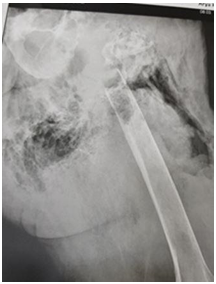

The patient was a 56-year-old male with pain, swelling, deformity in the thigh and pelvic, who had been referred to Arya private hospital in Rash, Iran. Patient had anemia symptoms and poor general condition. Case had left hip and knee flexion contracture, as well as the left proximal thigh and pelvic swelling. In addition, case had left hip joint mobilization and abnormal pain. X-ray showed a segmental destruction in the left proximal femur, as well as ischium, hip joint, iliac crest, left hemi-pelvis and femoral bone. Figure 1 shows gas in soft tissues between buttock muscles and swelling.

Figure 1: XR of hemipelvic, show distraction of iliac, iscum bone, hipe joint and proximal portion of femure.